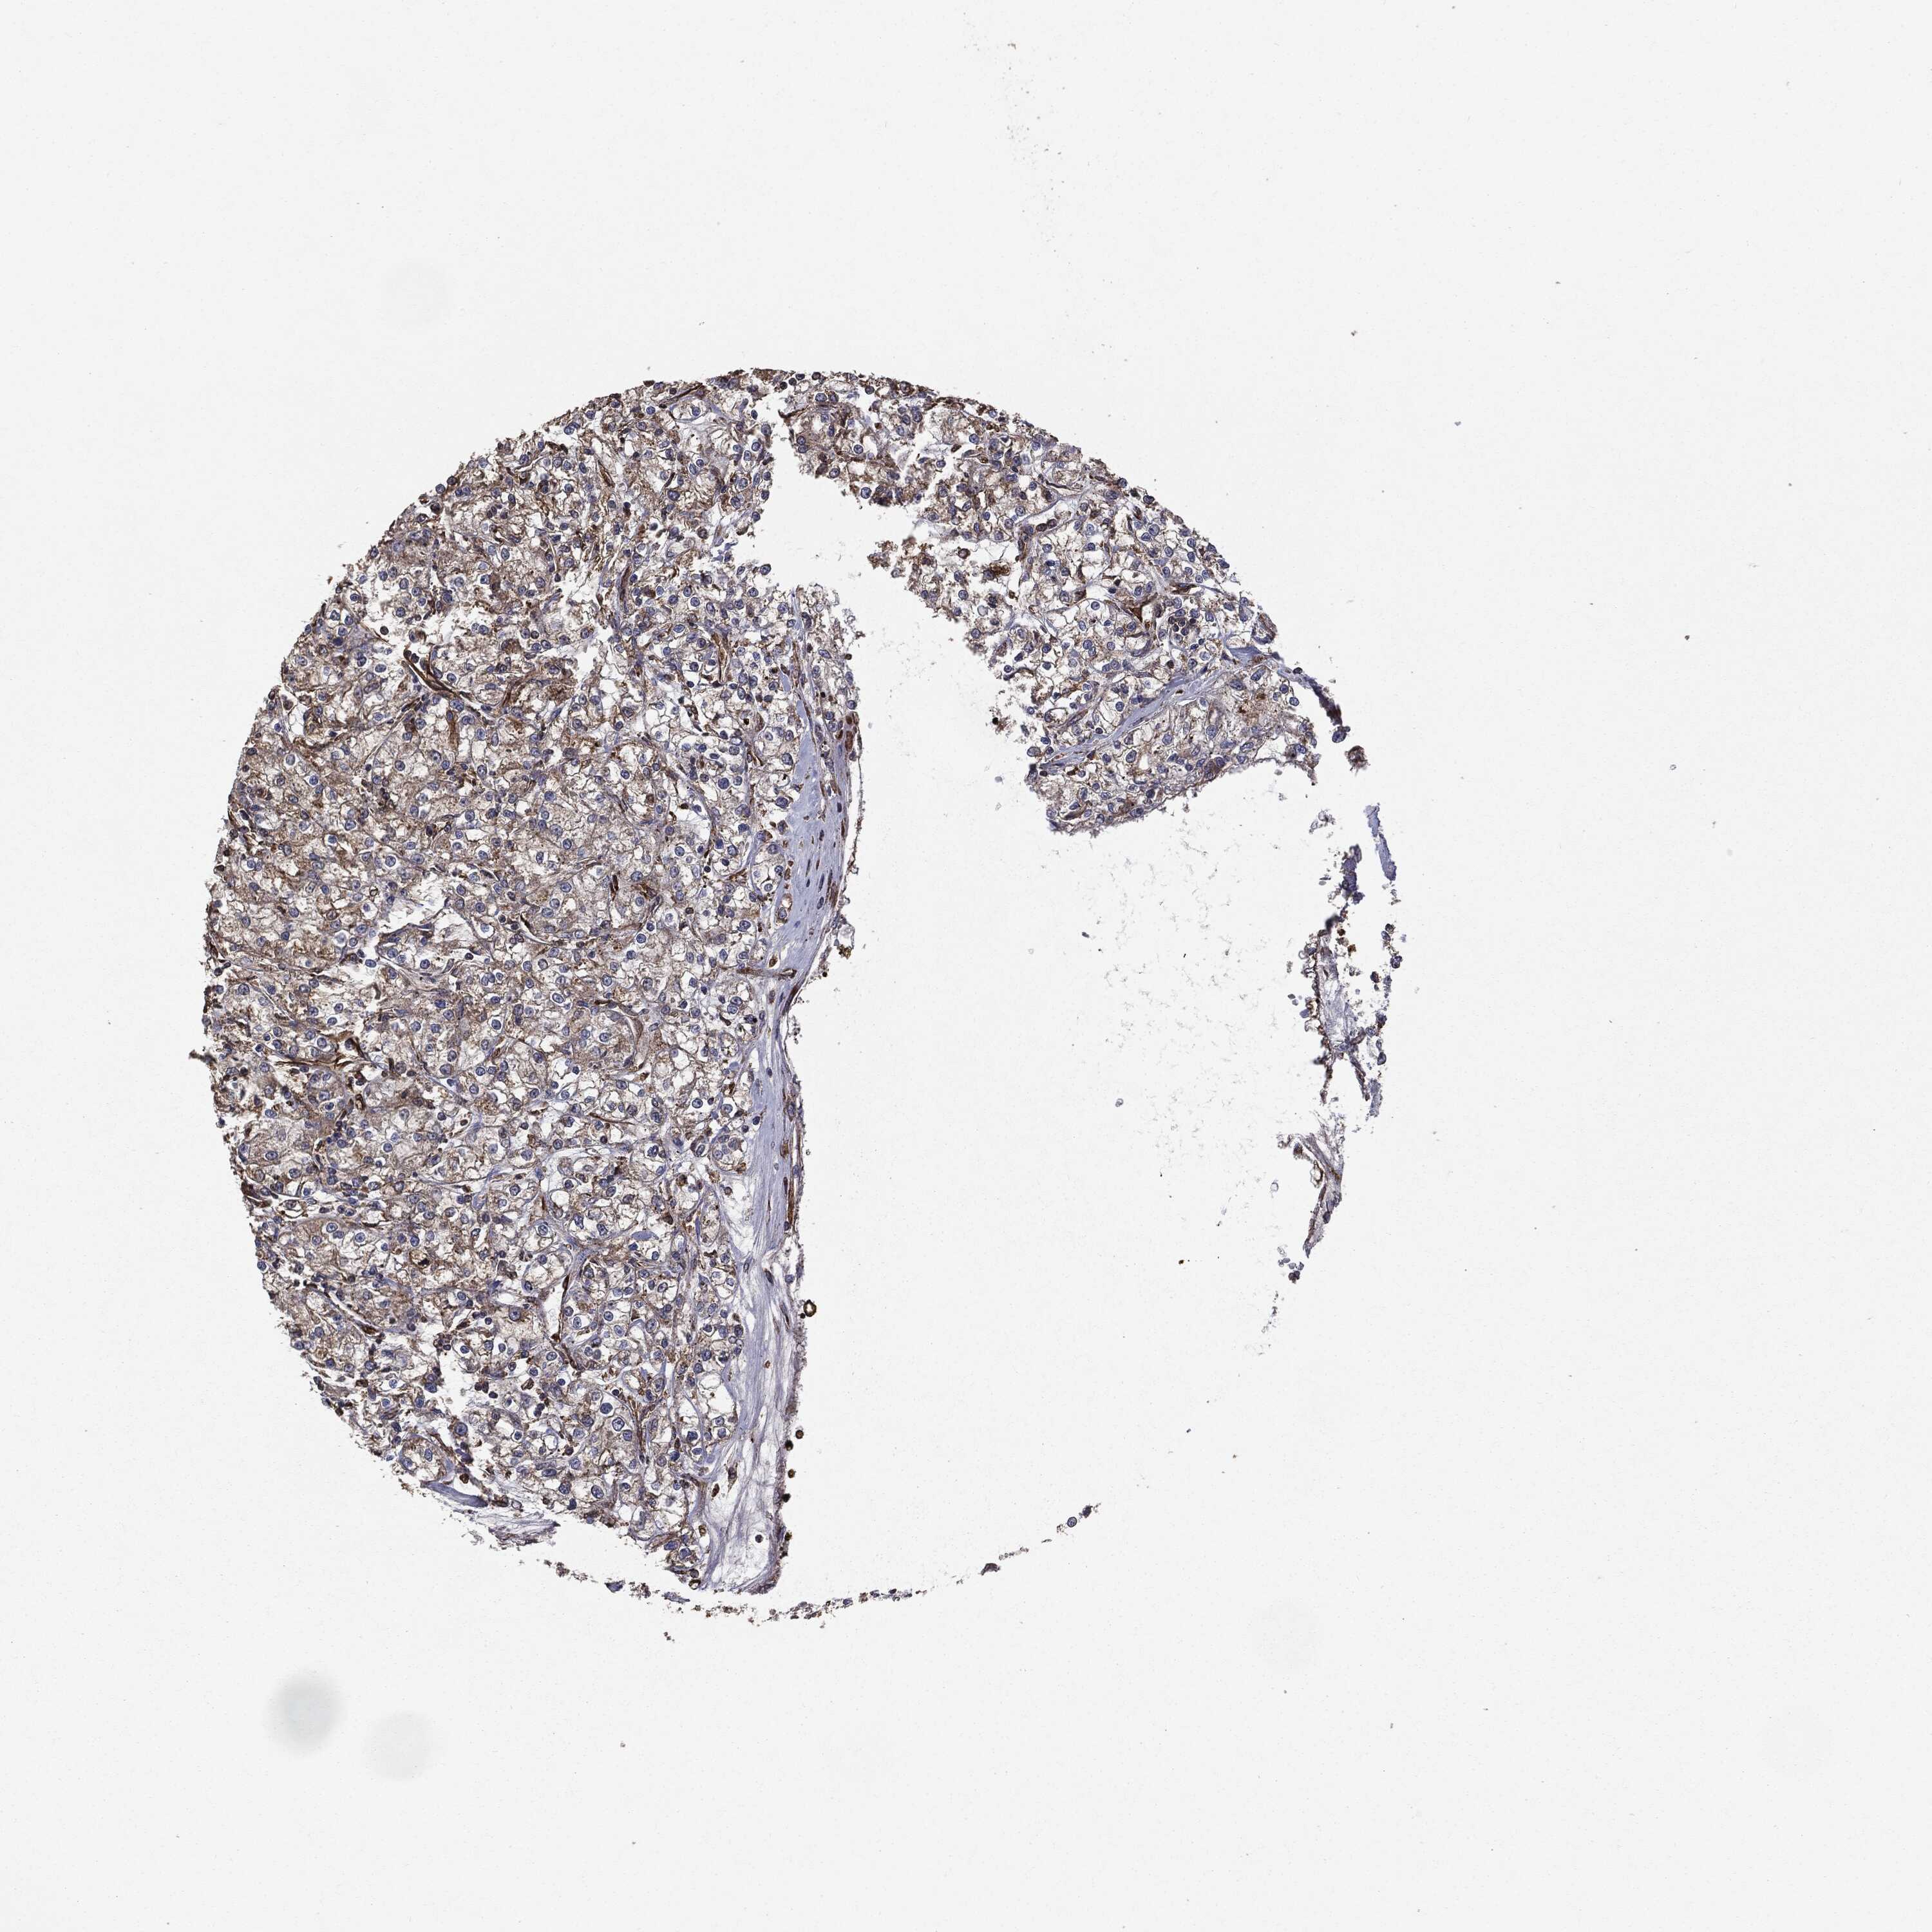

KIDNEY RENAL CLEAR CELL CARCINOMA (VALIDATION) - Interactive survival scatter ploti

The Survival Scatter plot shows the clinical status (i.e. dead or alive) for all individuals in the patient cohort, based on the same data that underlies the corresponding Kaplan-Meier plots. Patients that are alive at last time for follow-up are shown in blue and patients who have died during the study are shown in red.

The x-axis shows the expression levels (FPKM) of the investigated gene in the tumor tissue at the time of diagnosis. The y-axis shows the follow-up time after diagnosis (years). Both axes are complimented with kernel density curves demonstrating the data density over the axes. The top density plot shows the expression levels (FPKM) distribution among dead (red) and alive patients (blue). The right density plot shows the data density of the survived years of dead patients with high and low expression levels respectively, stratified using the cutoff indicated by the vertical dashed line through the Survival Scatter plot. This cutoff is automatically defined based on the FPKM cutoff that minimizes the p-score. The cutoff can be changed by dragging the vertical line or by entering a cutoff value in the square labeled "Current cut-off".

Under the Survival Scatter plot the p-score landscape (black curve; left axis) is shown together with dead median separation (red curve; right axis). Dead median separation is the difference in median mRNA expression between patients who have died with high and low expression, respectively. It is calculated as follows: median FPKM expression of dead patients with high expression - median FPKM expression of dead patients with low expression. This is intended to aid the user in visually exploring custom cutoffs and the associated p-scores and dead median separation.

Individual patient data is displayed and can be filtered by clicking on one or more of the category buttons on the top of the page. Categories describing expression level and patient information include: high, low, alive, dead, female, male and tumor stages. The scale of the x-axis can be toggled between linear and log-scale by clicking on the "x log" button. Mouse-over function shows TCGA ID, patient information and mRNA expression (FPKM) for each patient.

& Survival analysisi

Kaplan-Meier plots summarize results from analysis of correlation between mRNA expression level and patient survival. Patients were divided based on level of expression into one of the two groups "low" (under cut off) or "high" (over cut off). X-axis shows time for survival (years) and y-axis shows the probability of survival, where 1.0 corresponds to 100 percent.

MTOR is not prognostic in Kidney Renal Clear Cell Carcinoma (validation)

: 11.8

Average pTPM 12.9

Number of samples 100